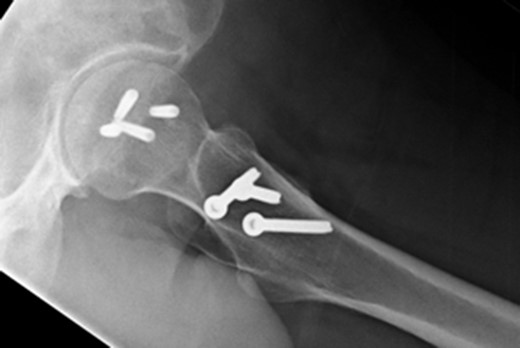

In addition to the bony injury, labral detachment and tearing were noted (later repaired with suture anchors). The femoral head was comminuted and had areas of missing articular cartilage especially posteriorly and superiorly with a 1 × 1 cm2 area of full thickness cartilage loss (Fig. 4). The weight-bearing zone was relatively unaffected. The ligamentum teres had to be released to allow fracture reduction and fixation with four headless compression screws (Fig. 5). A good fixation was achieved. Microfracture was performed on the articular cartilage defect. The femoral head, fracture fragment and microfracture site were bleeding and appeared viable.

Intraoperative view of the femoral head after fixation with headless compression screws.

At 14 months postoperative, the patient is pleased with his progress. There is no radiographic evidence of avascular necrosis at this stage (Figs 6 and 7). He regularly participates in activities such as cycling, and scores well on the modified Harris Hip Score (81/100), non-arthritic hip score (92.5/100) and SF-12 (41/48).